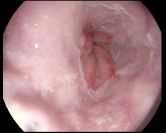

4.1.7 Gastrointestinal endoscopy

Endoscopies are used to detect diseases in the human digestive system. Images from inside the gastrointestinal tract can be used to help doctors detect diseases early. The used dataset 777https://www.kaggle.com/datasets/abdallahwagih/kvasir-dataset-for-classification-and-segmentation contains eight image categories of the digestive system obtained through the endoscopy imaging technique, as shown in Fig. 8. There are a total of images that can be used in training and testing machine learning algorithms.

Table 1 provides a detailed summary of the datasets used in this study, highlighting the total number of images in each dataset, the distribution between training and testing sets, and the specific classes represented. Each dataset corresponds to a particular medical imaging domain with distinct classes relevant to diagnosing specific conditions. Also, Fig. 9 presents a representative image from each dataset, allowing for a visual comparison of the diverse tones, patterns, and textures present across the datasets. Such diversity in visual characteristics highlights the need for a robust model that can handle all image characteristics.